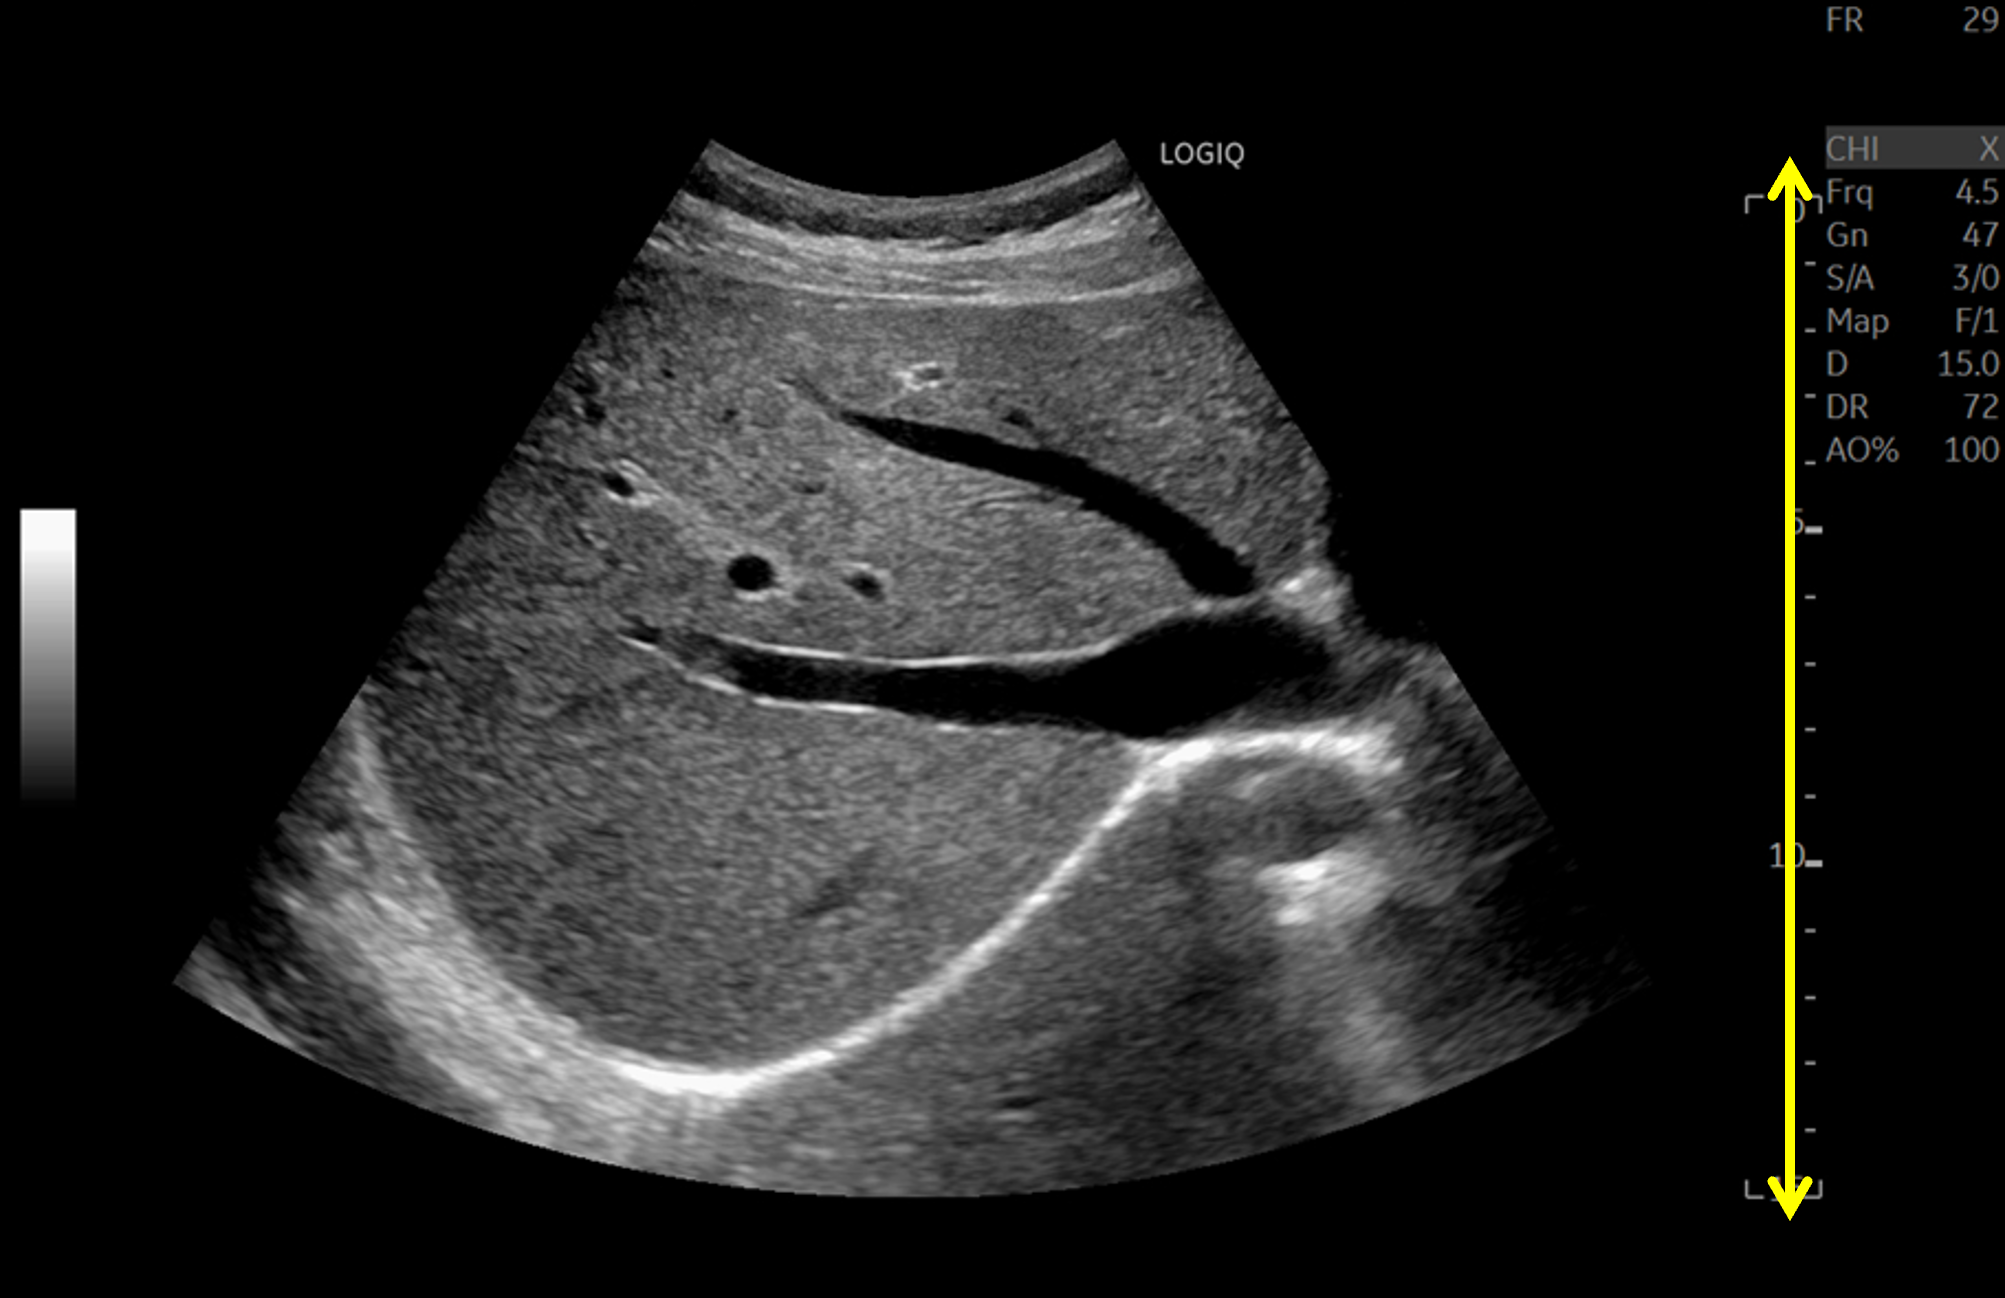

| 従来装置ではフォーカス近傍が明瞭に描出されているが、フォーカス以外の部分は明瞭に描出できておらず、関心領域に応じてフォーカスの位置を適宜変更する必要がある。LOGIQ Fortisでは、フルフォーカスにより浅部も深部も明瞭に描出され、フレームレートも高い。 |